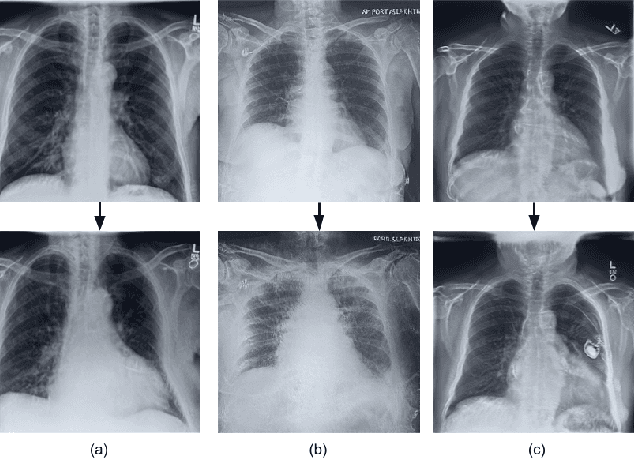

Deep learning models used in medical image analysis are prone to raising reliability concerns due to their black-box nature. To shed light on these black-box models, previous works predominantly focus on identifying the contribution of input features to the diagnosis, i.e., feature attribution. In this work, we explore counterfactual explanations to identify what patterns the models rely on for diagnosis. Specifically, we investigate the effect of changing features within chest X-rays on the classifier's output to understand its decision mechanism. We leverage a StyleGAN-based approach (StyleEx) to create counterfactual explanations for chest X-rays by manipulating specific latent directions in their latent space. In addition, we propose EigenFind to significantly reduce the computation time of generated explanations. We clinically evaluate the relevancy of our counterfactual explanations with the help of radiologists. Our code is publicly available.